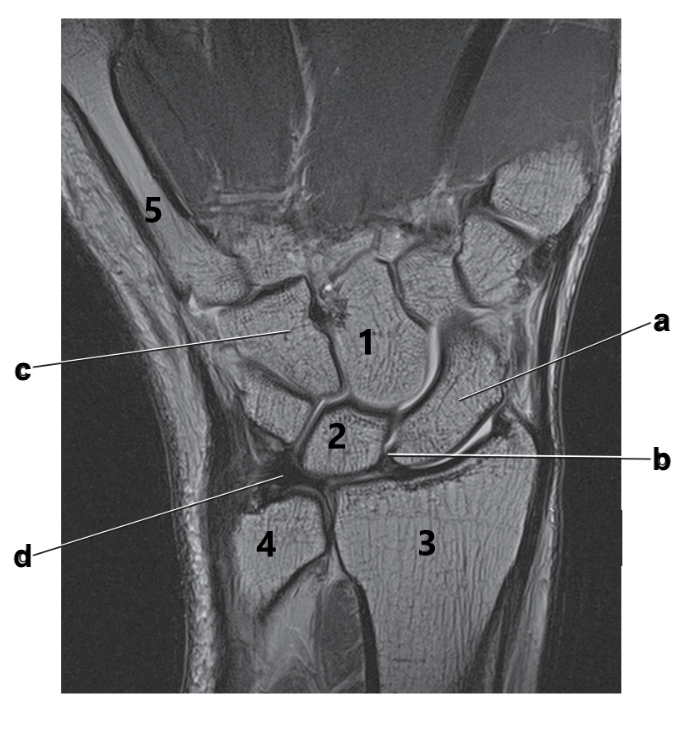

Scaphoid

Hook of the hamate

Ulna

Triangular fibrocartilage complex

Flexor retinaculum